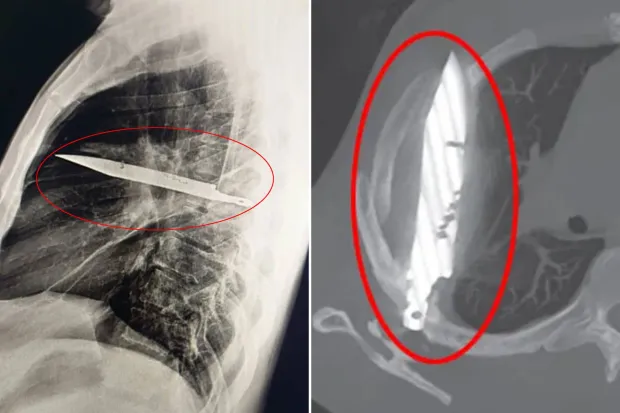

A Tanzanian man strolled into a hospital with a pesky nipple infection, only to discover he’d been carrying a knife blade in his chest for eight years! Talk about a stab in the dark. Doctors were stunned, but this guy’s been living his best life, oblivious to his inner cutlery.

Man with Sore Nipple Shocked to Learn He Had Knife Blade in His Chest for 8 Years